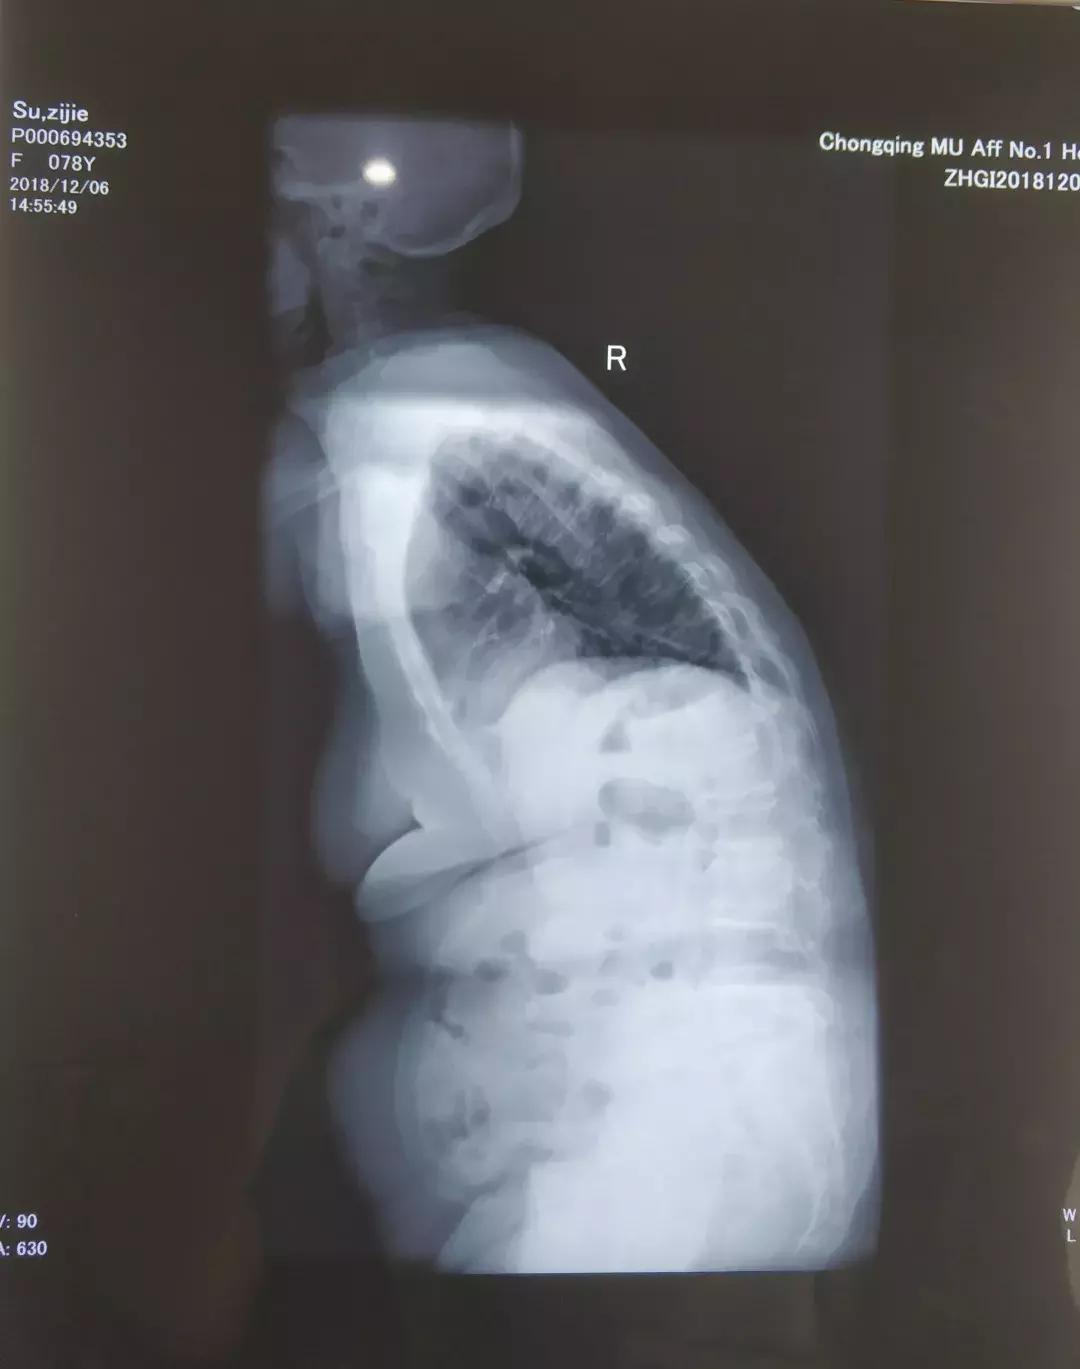

苏奶奶治疗前的脊椎情况

首次评估:脊椎活动度不足、核心肌肉无力导致无法伸直,但无疼痛感。

上图:训练之前在医院拍的片子

下图:在术康经过半年训练后的情况